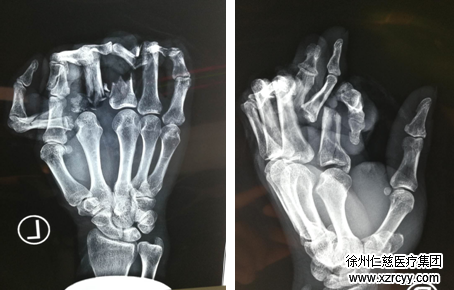

“赶快,去sararz,看手指能不能保住。”简单包扎后,剧痛难忍的李阿姨立即和家人第一时间驱车赶往必威官方首页官网betway。经诊断,李阿姨双手2-5指离断,其中双手小指完全离断,双手2-4指仅肌腱相连……更让医生担心的是,李阿姨多个手指为脱套性离断,血管挫伤非常严重,血管修复术后形成血栓的风险也相对较大……

为了保住李阿姨受伤的8根手指,再复杂的情况,医生们也要迎难而上!于是,一场“非同寻常”的手术开始了! 手外科三病区陈步国主任和吴尧医生同时进行手术,左右两边同时“开战”,为李阿姨的左右手进行断指再植。“两只手若不同步开展手术的话,断指时间超过8-10小时,手指成活率就非常低了。”

清创、骨折、关节融合内固定、修复肌腱血管神经……每一步手术过程都在严谨而细心地进行着。经过近8个小时的努力,李阿姨的伤口最后一针缝合完毕,双手2-4指成功再植,左小指成功种植,手术一切顺利。